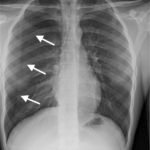

Initial chest radiograph showed a 50% right-sided pneumothorax with no mediastinal shift, which can be identified by the sharp line representing the pleural lung edge (see arrows) and lack of peripheral lung markings extending to the chest wall. While difficult to accurately estimate volume from a two-dimensional image, a 2 cm pneumothorax seen on chest radiograph correlates to approximately 50% volume.1 The patient underwent insertion of a pigtail pleural drain on the right and repeat chest radiograph showed resolution of previously seen pneumothorax. Ultimately the pigtail drain was removed and chest radiograph showed clear lung fields without evidence of residual pneumothorax or pleural effusion.